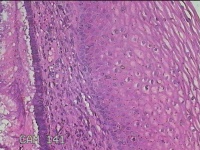

宫颈6点外缘、9点组织

性别

女

年龄

18岁

临床诊断

宫颈炎性疾病

一般病史

宫颈高危HPV感染

标本名称

大体所见

1.“宫颈6点外缘组织”:灰白粉红色不规则组织0.7x0.5x0.3cm两块。 2.“宫颈9点组织”:灰白粉红色不规则组织0.5x0.3x0.2cm一块。

良性病变。